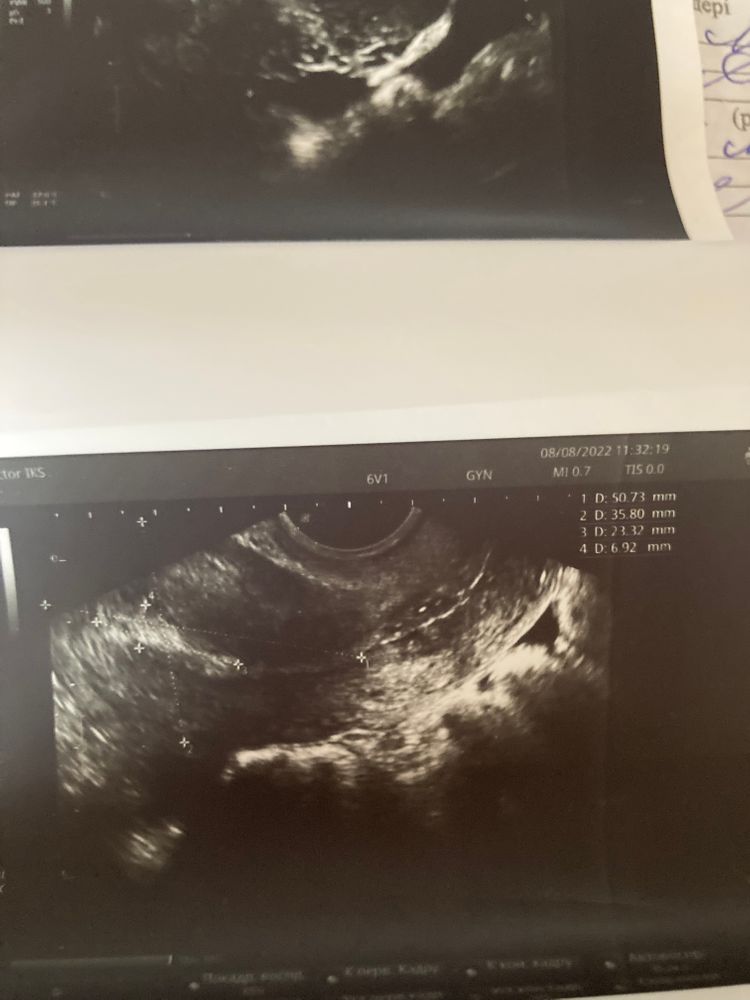

УЗИ на 19ДЦ Жидкость за маткой 3-4 дпо